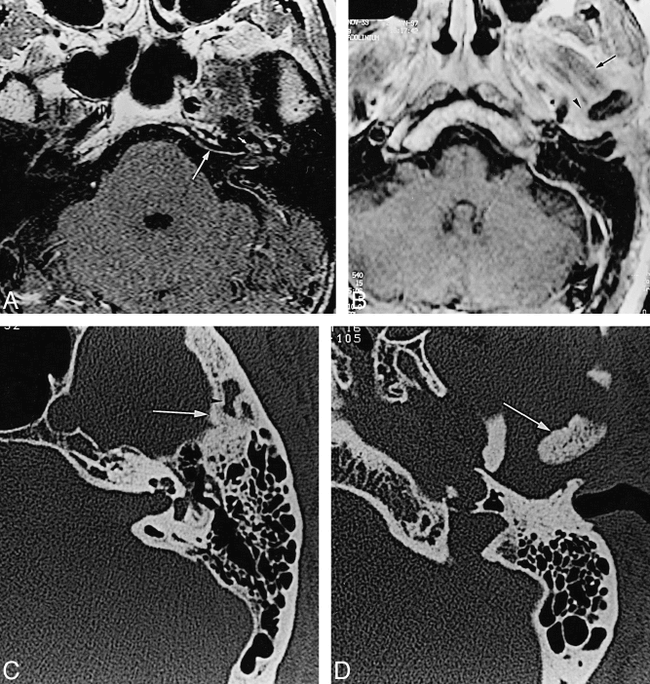

57-year-old man with SAPHO syndrome.

A, Axial contrast-enhanced T1-weighted MR image (500/15) reveals focal enhancement of the dura (large arrow) of the temporal bone, spreading into the internal auditory meatus with enhancement of the cochlea (small arrow). An enhancing soft-tissue mass of the middle ear, outlining the bony ossicles, is also present.

B, Axial contrast-enhanced T1-weighted MR image of the infratemporal fossa (540/15) (1 cm below A) shows a large soft-tissue mass around the TMJ (arrowhead), involving the lateral pterygoid muscle (arrow). Note the low intensity signal of the bone marrow of the condyle.

C, Axial CT scan of the left temporal bone shows abnormal endosteal sclerosis of the temporal squama (arrow) with subcortical erosions (arrowhead). A soft-tissue mass (arrowhead) engulfs the incudomalleal joint.

D, Axial CT scan (2 cm below C) shows osteosclerosis of the mandibular ramus (arrow).

Contrast-enhanced MR imaging of the brain showed focal enhancement of the dura covering the endocranial part of the left temporal bone, extending into the internal auditory meatus to the modiolus and cochlea (Fig 1A). Associated enhancement of the epitympanic part of the tympanic cavity was shown. The T2-weighted images showed normal high signal of the labyrinthine fluid and normal vestibulocochlear nerve. T1-weighted images showed a large soft-tissue mass involving the region of the left TMJ (Fig 1B). The capsule of the TMJ was thickened and enhanced intensely. No TMJ effusion was noticed. The bone marrow of both the mandibular ramus and the condyle displayed abnormal low signal intensity on T1- and T2-weighted images, and did not enhance after contrast administration.

High-resolution CT (performed the same day as the MR study) showed cortical bone erosions of both the temporal squama and the condyle and diffuse endosteal sclerosis involving the mandibular condyle and ramus (Fig 1C and D). The temporal squama was partially resorbed with areas of bone remodeling. The lesion of the temporal squama extended posteriorly to the petrotympanic suture, sparing the tympanic and petrous bones, anteriorly on the greater wing of the sphenoid, and inferomedially on the sphenoid bone. The glenoid fossa was enlarged relative to the normal contralateral one, and no intra- or periarticular calcifications were evident. The normally aerated middle ear was partially filled by a soft-tissue mass, engulfing the lateral part of the incudomalleal joint. Neither the soft-tissue mass nor bony erosions were present in the external auditory canal.